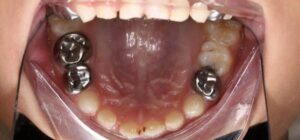

- Bảo vệ răng sau điều trị tủy

Mão SSC giúp bao phủ toàn bộ thân răng, giảm nguy cơ nứt vỡ và tái nhiễm khuẩn.